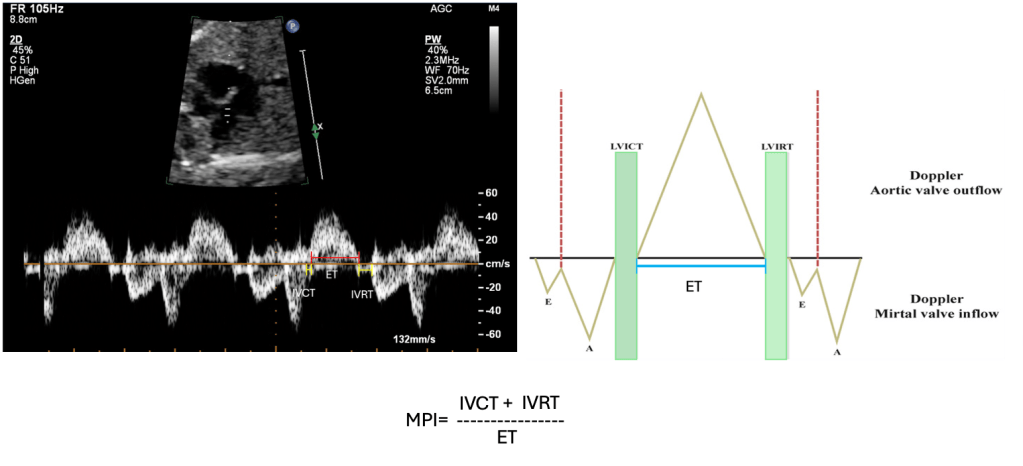

The Modified Myocardial Performance Index is a load-independent Doppler-derived metric that reflects combined systolic and diastolic myocardial performance by analysing key parts of the cardiac cycle:

- Isovolumetric Contraction Time (ICT): The interval after atrioventricular valve closure and before semilunar valve opening, representing ventricular contraction buildup

- Isovolumetric Relaxation Time (IRT): The period after semilunar valve closure and before atrioventricular valve opening, reflecting ventricular relaxation

- Ejection Time (ET): The duration of active ventricular blood ejection

The formula is: (IVCT+IVRT)/ET

This captures both ventricular contraction (systolic) and filling (diastolic) phases in a single index.